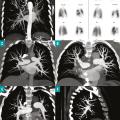

L’hypertension pulmonaire thromboembolique chronique (HTP-TEC) est une forme d’hypertension pulmonaire liée, d’une part, à une obstruction chronique des artères pulmonaires par du matériel fibreux, et, d’autre part, à une microvasculopathie secondaire. Elle survient le plus souvent après une ou plusieurs embolies pulmonaires (EP)…